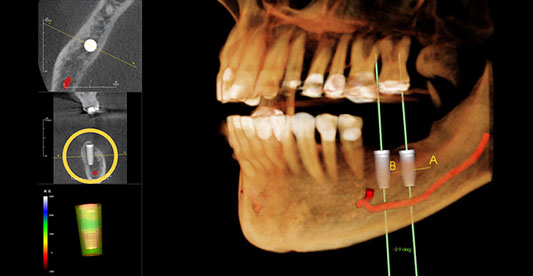

01신경손상을 막아주는 3D-CT3D-CT를 통해 신경손상의 원인을 사전에 차단삼성올바른치과는 부작용 걱정없이 임프란트 시술을 위하여 3D-CT를 이용하여 임플란트를 식립할 환자의 뼈의 상태를 정밀하게 분석하고, 신경선이 지나가는 미세한 부분까지 확인하여 신경손상의 원인을 사전에 차단하여 정확하고 안전하게 임플란트를 식립합니다.

02부작용을 줄이는 사전 시뮬레이션실제 환자의 얼굴뼈와 일치하는 영상으로 모의수술을 진행3차원 입체영상을 바탕으로 환자의 얼굴뼈와 일치하는 영상을 만들어 모의 수술을 진행하여 환자에게 가장 적합한 수술방법을 찾아냅니다. CT장비를 이용하여 뼈의 0.1mm까지 분석하며 신경손상, 잇몸통증 등 수술중이나 수술후의 합병증과 불편함을 줄여 부작용없이 안전한 치료가 가능합니다.